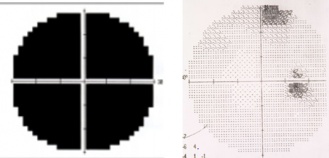

Patients may present with varying levels of decreased visual acuity (in addition to the visual field defects above). There will be an ipsilesional relative afferent pupillary defect (RAPD). Band type optic atrophy may be seen on fundus exam in cases which involve nasal fibers. In the junctional scotoma the band atrophy is in the contralesional eye (superotemporal visual field loss) and in the junctional scotoma of Traquair will be in the ipsilesional eye if the defect is monocular and a temporal hemianopsia is present. In the nasal hemianopic variety (rare) of the junctional scotoma of Traquair the optic atrophy will be more likely in the hour glass (temporal fiber atrophy) and not the band configuration (nasal fiber atrophy). Figure 1 shows the junctional scotoma of Traquair and Figure 2 shows the junctional scotoma. It is important to note, that attention to the asymptomatic eye should always be meticulous as failing to do a confrontation visual field testing may allow for missing a junctional scotoma, keeping in mind the confrontation fields are only useful when the visual field defect is picked up.